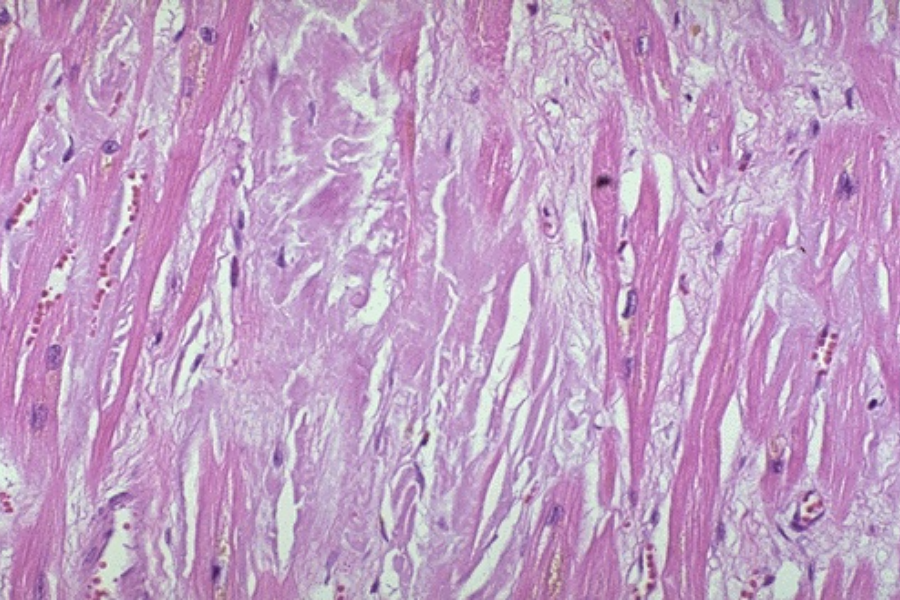

histologische Bilder

adultes Myokard

adultes Myokard

Pathology Residency and Fellowship Program, Brown University, Access 23. October 2022

Elliott P, McKenna WJ (2004) Lancet 363:1881-1891

Internet Pathology Laboratory , University of Utah, Access 23. October 2022

Thoracic Pathology, Cardiac Hemochromatosis, Access 23.October 2022